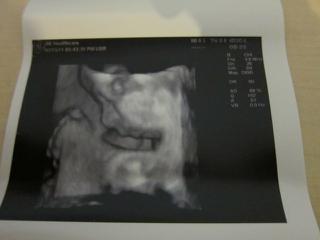

bolo to uzasne, 😵 fakt to stalo za to, sestricka najprv vsetko pomerala, skontrolovala, babo je v poriadku a definitivne sa potvrdilo ze to bude nase vytuzene dievcatko, 😵 podla sestricky je to iste na 1000%. 🙂

Babo sa nenechalo rusit a cele sono prespinkalo, (ani sa necudujem, mali sme rusnu noc, chytila ma choroba tak so mnou ponocovala, 😅 ),

na videu je sice stale kludnucka a len sem tam sa pohmyri ale aspon sa lepsie dalo zachytit foto, aj ked si davala stale rucicku pred tvaricku a niekedy tam ta rucicka zavadzala. 😉

Ale aj tak som maximalne spokojna, stale sa neviem vynadivat na bambulku, 😵 je uzasna, meria 37 cm a vazi 1150 g, zodpoveda 27tt, (dnes zacinam 28 tt tak mi to sedi.)

Kuk na foto a dufam ze pridas aj ty. 🙂

Ta prva foto je trochu rozmazana nozicka a foto pod nou dokaz kavoveho zrnka, 😉 na dvd je to lepsie vidiet, tam je to z roznych uhlov. 😉